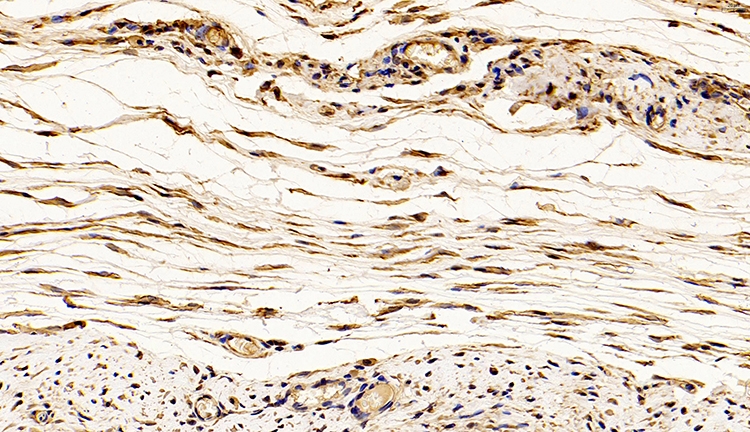

免疫荧光通过抗体与示踪物质结合,利用抗原-抗体结合反应,进而对抗原所在的细胞或组织进行定性或定量。

由于荧光素所发的荧光可在荧光显微镜下检出,荧光素受激发光的照射而发出明亮的荧光,可以看见荧光所在的细胞或组织,利用定量技术测定含量,从而可对抗原进行细胞定性和定位分析。

免疫荧光实验可以快速直观的显示所检测蛋白的细胞定位。